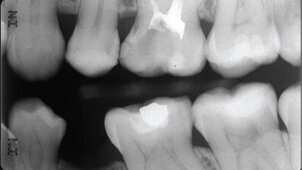

Η παρουσίαση ενός κλινικού περιστατικού σε ενός χρόνου επανεξέταση, δείχνει τη λειτουργικότητα της αποκατάστασης, ενώ η σύνθετη ρητίνη συγκολλήθηκε 12 λεπτά μετά την αρχική πήξη του υλικού. Ύστερα από ένα χρόνο η αποκατάσταση δεν παρουσίασε αλλοιώσεις και ο ακτινογραφικός έλεγχος δεν έδειξε την εμφάνιση δευτερογενής τερηδόνας.